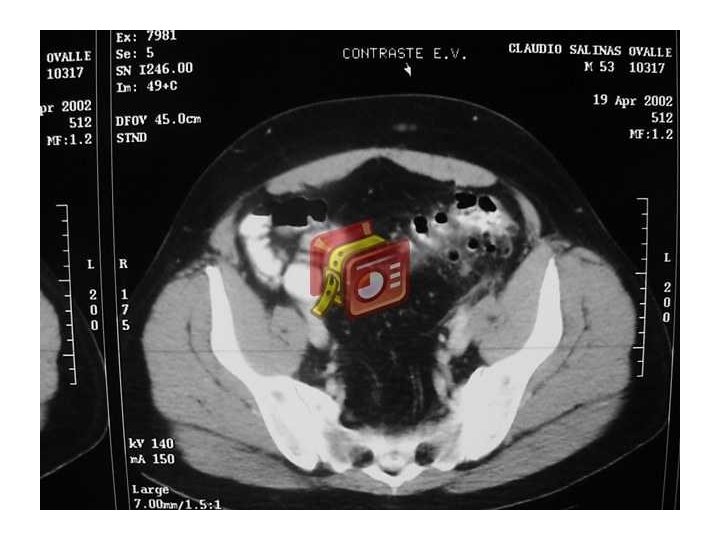

Diverticulitis • Inflamación divertículo y tejido pericolónico • 10 a 20% de los pacientes que conocen su enfermedad la desarrollan • Clínica: A veces pobre en el anciano – Dolor intenso abdominal (FII), irritación peritoneal, fiebre, abdomen quirúrgico. Leucocitosis – Perforación: absceso, neumaturia, fístulas • En diagnóstico útil Ecotomografía y TAC • Colonoscopía en frío confirmar patología y descartar neoplasia • 22– 30% de los individuos que presentan un primer episodio de diverticulitis presentarán un segundo episodio

Divertículos de colon